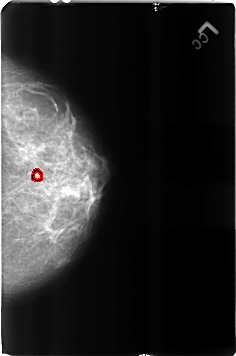

B_3160_1.RIGHT_CC

FILE: B_3160_1.RIGHT_CC.OVERLAY

TOTAL_ABNORMALITIES 1

ABNORMALITY 1

LESION_TYPE MASS SHAPE ROUND MARGINS N/A

ASSESSMENT 2

SUBTLETY 3

PATHOLOGY BENIGN_WITHOUT_CALLBACK

TOTAL_OUTLINES 1

BOUNDARY